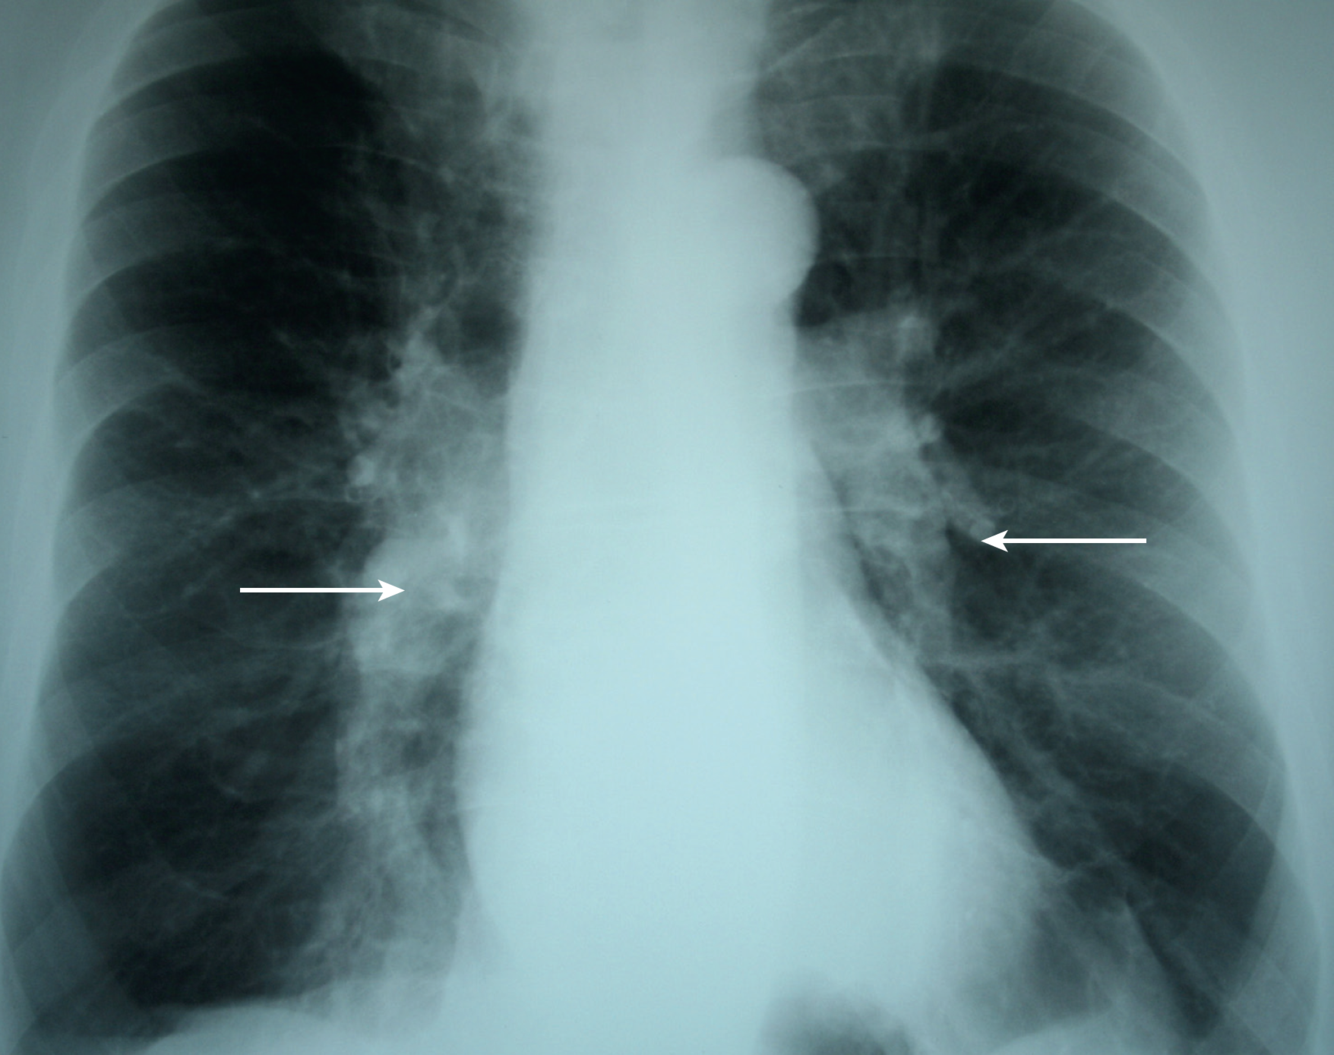

What are you looking for in CXR and CT chest in COPD patients?

CXR: hyperexpansion, increased retrosternal airspace (≥2.5cm), radiolucent bullae (specific for COPD), features of pulmonary HTN (prominent pulmonary arteries)

T: spirometry (irreversible obstruction), PFT (inc TLC, low DLCO), CXR (hyper-expansion, prominent pulmonary vasculature), CT chest (burden of emphysematous disease)